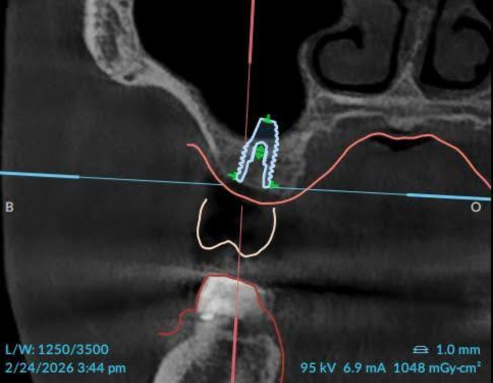

Lateral Window sinus grafting: Before & After

Before